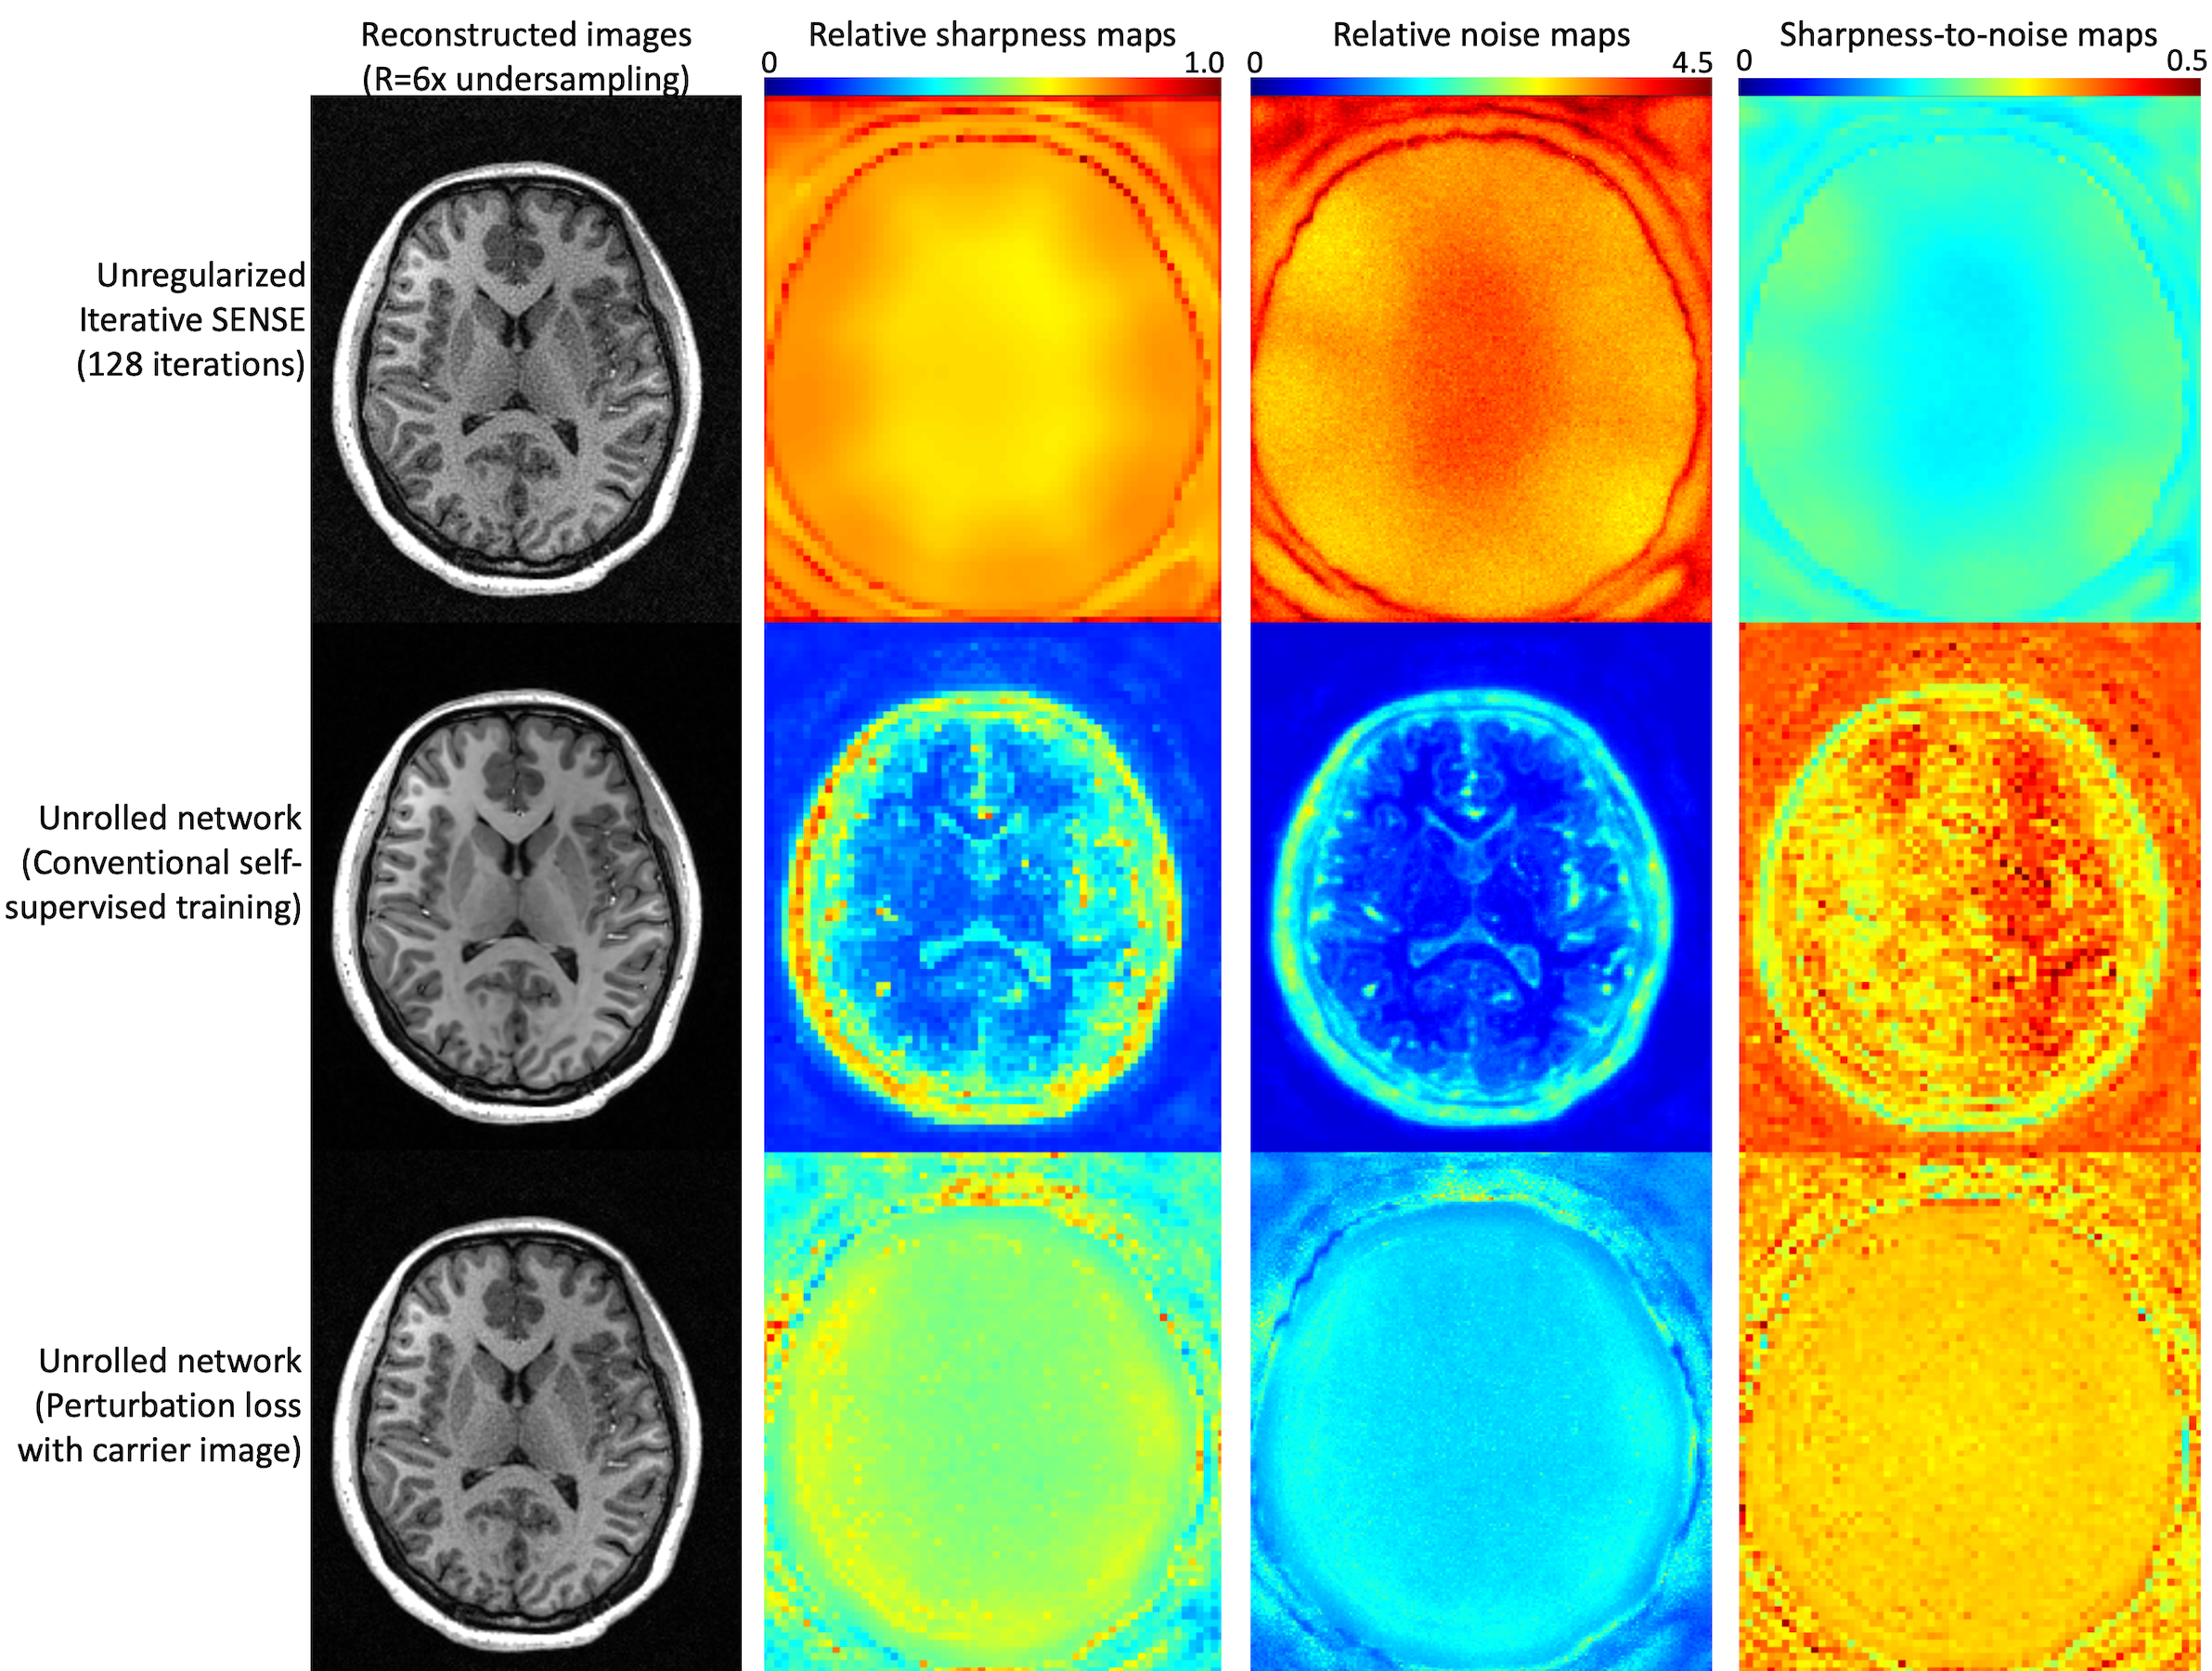

Reconstruction performance was quantified by computing the relative noise of reconstructed images (using the pseudo-replica method) and by computing the relative sharpness, defined as the fraction of a small perturbation added to an input voxel that is retained in that location after reconstruction (closely related to the PSF). The ratio of sharpness-to-noise gives a summary of overall performance. We compared unregularized iterative SENSE (128 iterations), an unrolled network using a self-supervised MAE loss, and an unrolled network using the proposed loss.

Figure 2 shows the reconstruction performance on an MPRAGE scan acquired with prospective 6-fold variable density Poisson disc acceleration. Iterative sense provides the sharpest image but suffers from extreme noise amplification, yielding a low sharpness-to-noise map. Self-supervised training yields a very low-noise image but with relatively poor sharpness. Furthermore, the sharpness and noise are anatomy dependent, making low-contrast detectability regionally variable. Interestingly, the overall performance of this training remains very high. The proposed loss function balances sharpness and noise amplification to maximize feature detectability. The sharpness is generally higher than with self-supervised loss but so is the reconstructed noise. The relative sharpness-to-noise is reasonably high and interestingly is not anatomy dependent.

The self-supervised loss function works very well, as shown by the relative sharpness-to-noise ratio in Figure 2 but achieves this success via aggressive noise suppression. The proposed loss optimizes small feature retention, which produces objectively sharper images but with more noise.

Figure 2: Comparison of reconstructions with 6x accelerated MPRAGE: (top) unregularized SENSE, (middle) unrolled DL network with conventional training, (bottom) unrolled DL network with the proposed perturbation loss. SENSE produces the sharpest image but with extreme noise amplification. A conventionally trained DL network produces a clean image but with compromised and anatomically dependent sharpness. A DL network with the proposed loss provides high relative sharpness yet limited noise amplification.